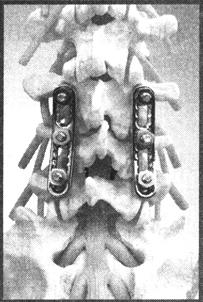

最初的椎弓根钉器械是螺钉加钢板的系统,如Roy-Camille系统和Stefee系统(图13-46)。但初期的螺钉直径细小,螺纹浅,钢板的强度也不足够,所以植骨愈合率低,并发症发生率较高。后来发展了螺钉加螺纹棒系统,如Dick、RF(图13-47)、AF。螺钉和棒的系统比钢板系统更坚固,而且棒可在多角度预弯,使用更灵活。但螺纹棒安装烦琐,费时费力,不利于进行提拉和撑开,棒的强度也不够。新一代的系统使用钛合金为原料,光滑的棒代替了螺纹棒,螺钉和棒的连接采用了上锁紧的螺母,如:Moss Miami、CD-Horizon(图13-48)、ISOLA、USS(图13-49)。这些椎弓根螺钉系统使用简单方便,复位效果好,钉棒的断裂也较前大大减少,故得到了广泛的应用。最新的椎弓根钉系统继续改良钉与棒之间的连接方式和提拉撑开的方法,以求获得更快捷的操作和更好的手术效果,如Monarch(图13-50)、TSRH-3D(图13-51)、USS Ⅱ。

图13-46 Depuy的VSP钉板系统,是改良的Stefee

图13-47 RF系统

图13-48 Sofamor的CD Horizon螺钉

图13-49 Synthes的USS脊柱创伤系统

图13-50 Depupy的Monarch系统

图13-51 Sofamor的TSRH-3D系统